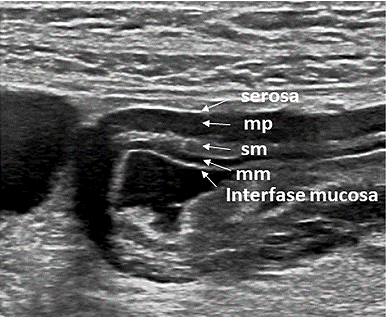

La correlación entre la anatomía y la apariencia ecográfica digestiva es considerada adecuada en la práctica clínica, aunque las diferentes interfaces acústicas que producen el aspecto ecográfico de capas no se corresponden exactamente con las diferencias histológicas. [12], [15] . Ecográficamente se diferencian hasta 5 capas ( IMAGEN 1 ) con alternancia de capas hiperecogénicas con hipoecogénicas, identificándose un patrón reproducible o “FIRMA DEL TUBO DIGESTIVO”.

La "FIRMA DEL TUBO DIGESTIVO" tiene cinco capas concéntricas que desde la luz al exterior son:

Mucosa: hiperecogénica

Muscular de la mucosa: hipoecogénica

Submucosa: hiperecogénica

Muscular propia: hipoecogénica

Serosa o Adventicia: hiperecogénica

Figura 1: Ecoestructura de la pared intestinal con alternancia de capas hiperecogénicas y capas hipoecogénicas. (15)